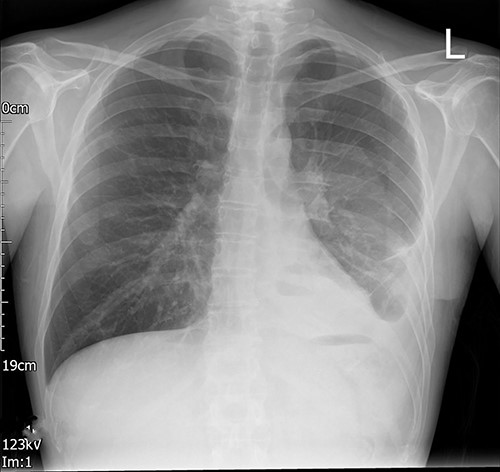

Left-sided uniportal VATS retrieval of the guidewire was done under general anesthesia (Video 1). The surgery was uneventful as was the post-operative recovery. The intercostal drain left in situ post-surgery was removed on a post-operative day (POD) 1 and the imaging done after the drain removal (Fig. 3) showed a significant decrease in pleural effusion with no guidewire in the chest cavity. He made a good recovery with an adequate physiotherapy assessment. The patient was discharged on a post-operative day (POD) 3. No follow-up was needed as he made a good recovery.

Left VATS post-operative posterior–anterior chest radiograph showing no guidewire in the left pleural cavity.